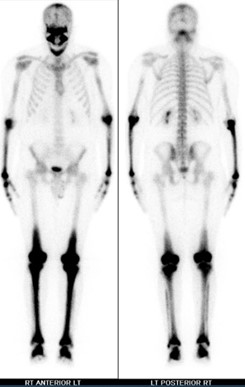

An evaluation for extracranial involvement was ordered and included a bone scan, PET scan, and cardiac MRI. Bone scan showed high-intensity trace uptake in the skull, mandible, predominantly distal long bones of the upper and lower extremities is consistent with widespread histiocytosis (Figure 3).

PET scan showed hypermetabolic uptake within the medullary portions of the diffuse abnormal lesions of the distal femurs, tibias, and fibulas, and cardiac MRI was unremarkable. The patient was started on vemurafenib and continued to show improvement in a 3-month outpatient follow-up.